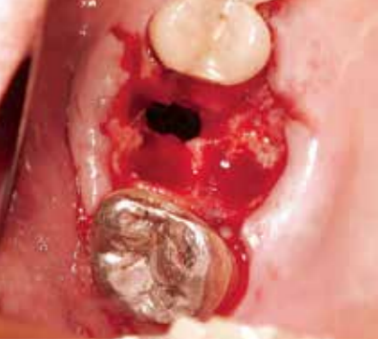

在穿孔直径大的情况下(有牙冠大小),无法获得自然闭合(图5),所以要马上转诊到专科医生处做修补手术。

图5 16牙冠大小的穿孔。可以看到窦内有掉入的牙齿。由于穿孔直径很大,取出掉入的牙根后,必须做修补手术